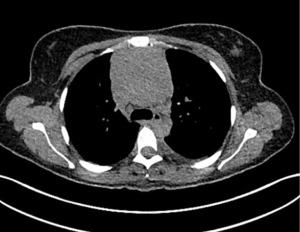

A thoracic computed tomography (CT) scan (Figure 2) revealed a large anterior-superior mediastinal mass of 80 mm × 67 mm with malignant left pleural effusion. The core biopsy was consistent with a myeloid sarcoma (MS), a rare extramedullary manifestation of acute myeloid leukemia (AML), according to World Health Organization (WHO) 2022 classification and the International Consensus Classification (ICC) 2022. The fluorine 18-labeled fluorodeoxyglucose (FDG) positron emission tomography (PET)-CT (Figure 3) showed increased FDG uptake by the mediastinal mass, the presence of numerous hypermetabolic lymph nodes on both sides of the diaphragm and a thickened left pleura. The bone marrow biopsy was negative for AML and a new large surgical biopsy of the mediastinal mass had to be performed for fresh tissue samples, in order to perform flow cytometry, molecular and cytogenetic analysis.